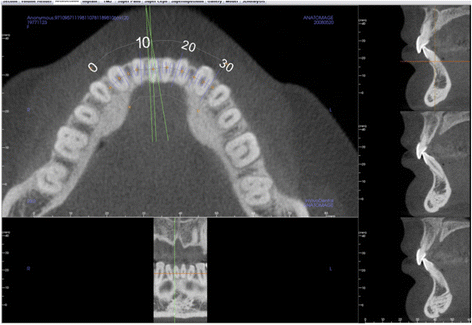

Using Anatomage Invivo5 CBCT software, sagittal slices were taken of the CBCT image through the middle of the root canal, at the midpoint of the long axis of the right central incisor (Fig. 1). From the sagittal slice of the center of the incisor, pretreatment measurements were taken for the buccolingual width at the apex and the alveolar crest (Fig. 2).

There are negative sequelae to orthodontic treatment when the bony support is narrow. Severe root resorption can be seen on CBCT in the mandibular incisors of high-angle cases after orthodontic treatment that cannot be seen clinically (Fig. 6). Our study found that high-angle subjects are more prone to root resorption beyond that expected for routine orthodontic treatment (Fig. 7). Root resorption after orthodontic treatment over 10 % was higher in high-angle compared to average- and low-angle subjects (22, 20, and 9 %, respectively). More alarming was that the high-angle subjects were at the highest risk of having the tooth penetrate the alveolar housing after orthodontic treatment (22 vs. 5 % in average-angle patients and 0 % in low-angle patients) (Table 2). Even though the percentage of individuals with root resorption over 10 % is high in the high-angle patients, Fisher’s exact test yielded a p value that was not statistically significant (p = 0.824). Fisher’s exact test also showed that the difference in the percentage of the sample population with the teeth penetrating the cortical plates was not statistically significant among the three groups (p = 0.138). This could be due to the small sample size of the lower angle patients.